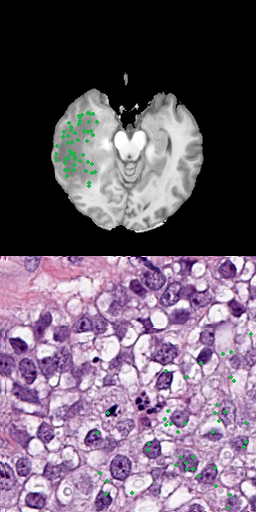

4.4.1 Sampling using Positive Points

One approach is to use several positive points as input data that represent the goal label [8]. Using points as input is a precise method, allowing to preserve fine segmentation details but requires more annotation effort. When large areas are annotated, this is especially problematic. Figure 3 shows samples for using 3, 10, 50 or 100 points for the radiology and pathology data.

Refer to caption

(a) 3 positive points

(b) 10 positive points

(c) 50 positive points

(d) 100 positive points

Figure 3: Results for different number of positive points without bounding box